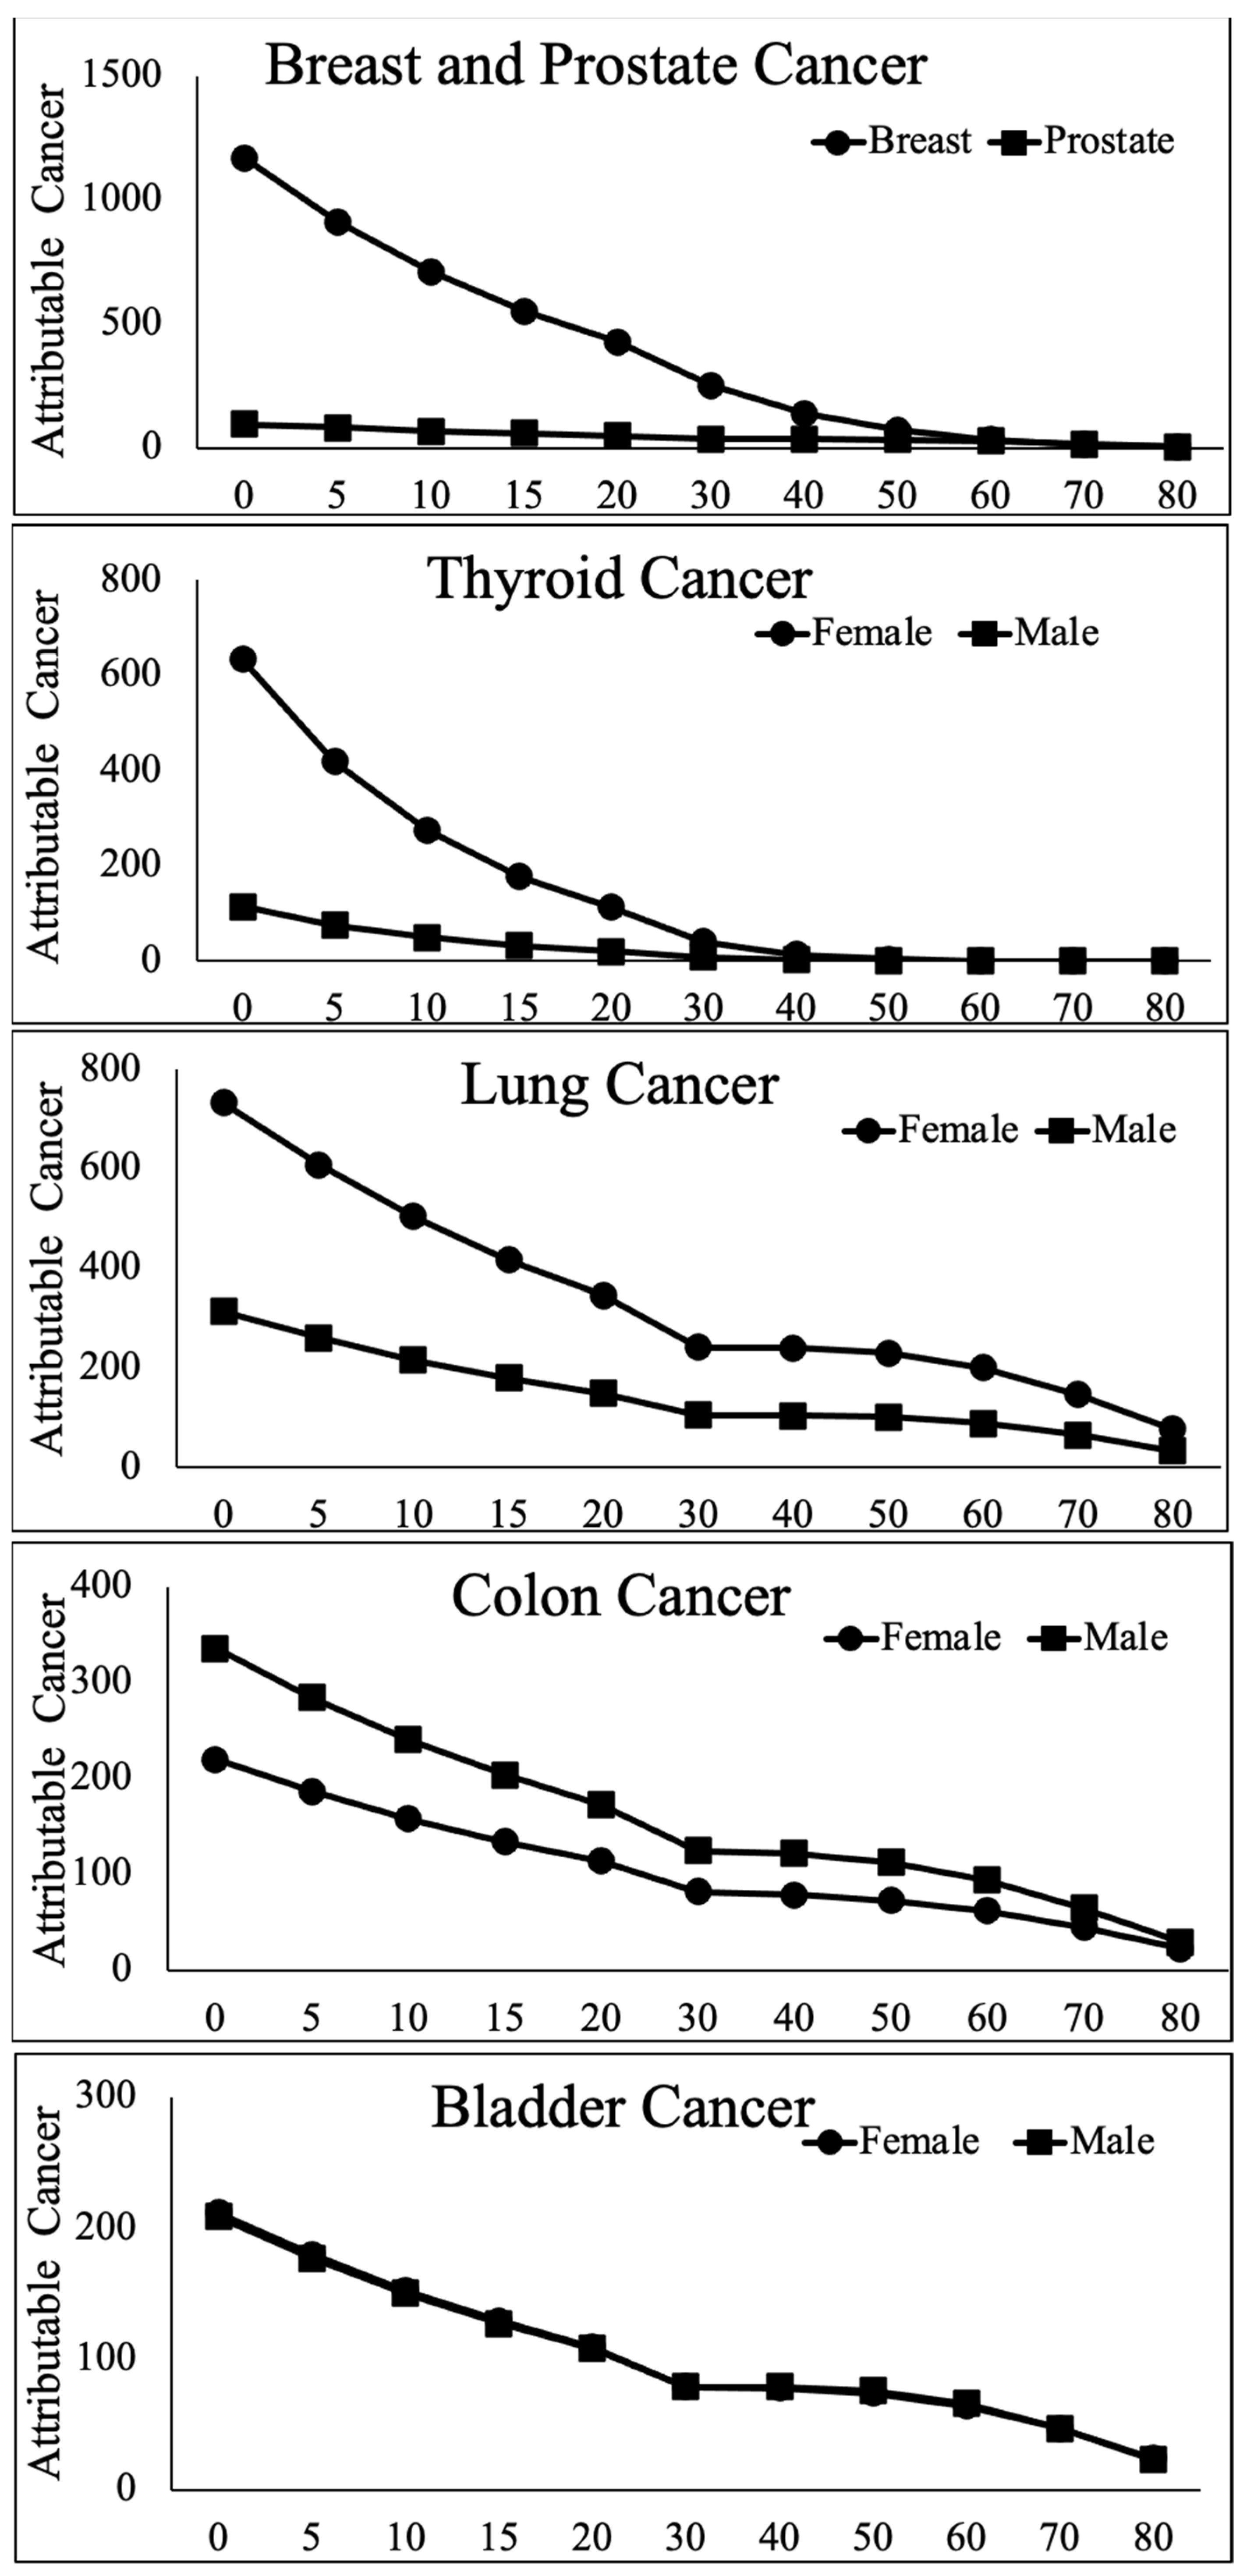

- Solid tumor incidence secondary to exposure following the atomic bombing of Hiroshima and Nagasaki, the largest cohort subjected to continued surveillance over more than 60 years, is markedly higher (~2-fold) in women.

- This excess risk varies by organ and age at exposure, with the largest sex differences (6- to 10-fold) found in female thyroid and breasts exposed between birth and menopause (~50 years old) when compared to males in the same age group.

- The risk of secondary breast or thyroid cancer in females decreases more steeply with age at exposure in females compared to males.

- The pattern of vulnerability is remarkably consistent across a variety of exposure mechanisms, radiation doses, mathematical models and risk metrics, such that young females are at a highly elevated risk of secondary solid tumors, especially breast and thyroid, when exposed to wartime, therapeutic or diagnostic radiation.